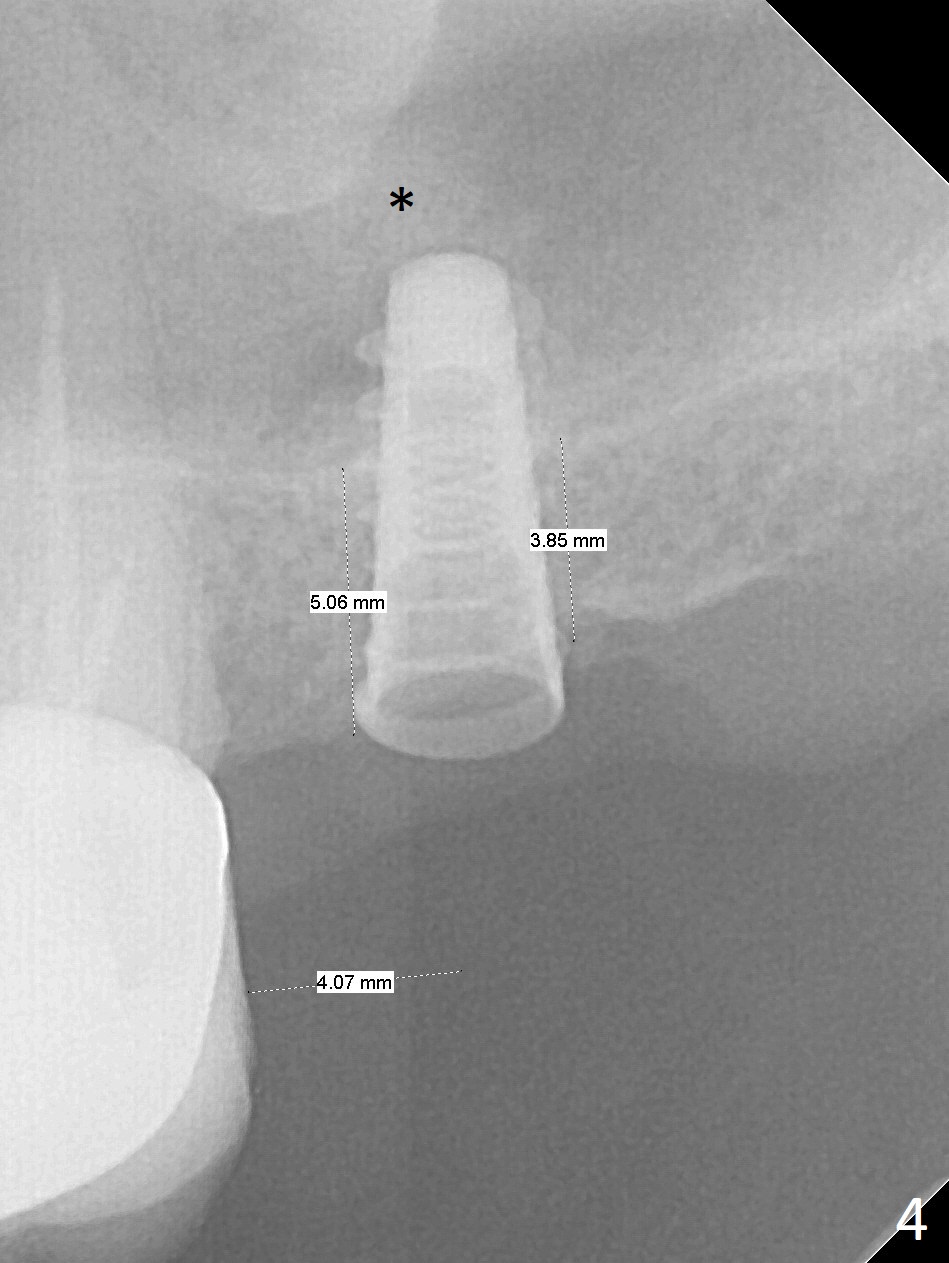

After removal of the mesial (M) and distal (D) residual roots of the tooth #15 (Fig.1,2), Magic Split is used to test bone density (high), followed by Magic Drills from Magic Sinus Lift Kit (for 4 mm) and Magic Surgical Kit (for 5 mm). It appears that the sinus floor has been perforated with the intact sinus membrane. Following minimal use of Magic Lifter, Vanilla Graft is inserted (Fig.3,4 *) and a 4x9 mm dummy implant is placed. After placement of more allograft (Fig.5 *), a 5x7 mm implant is placed with ~ 35 Ncm. With placement of a 5.5x4(2) mm abutment, an immediate provisional is fabricated to close the socket. Six months postop, the bone graft remains in the sinus around the apical end of the implant (Fig.6 *), while there seems no bone loss coronally (Fig.7). In fact there is, as shown later (Fig.8-11 < and lingual (L)). The crown is recemented 6 months post cementation (due to short abutment). The abutment seems to be incompletely seated. When the crown at #14 is reprep following #13 implant, the abutment screw is being untightened, the crown dislodges first. The abutment is confirmed short with more than enough occlusal clearance. After use of 5.5 and 6.0 mm bone profile drills, a 5x4(3) mm abutment is placed with complete seating.